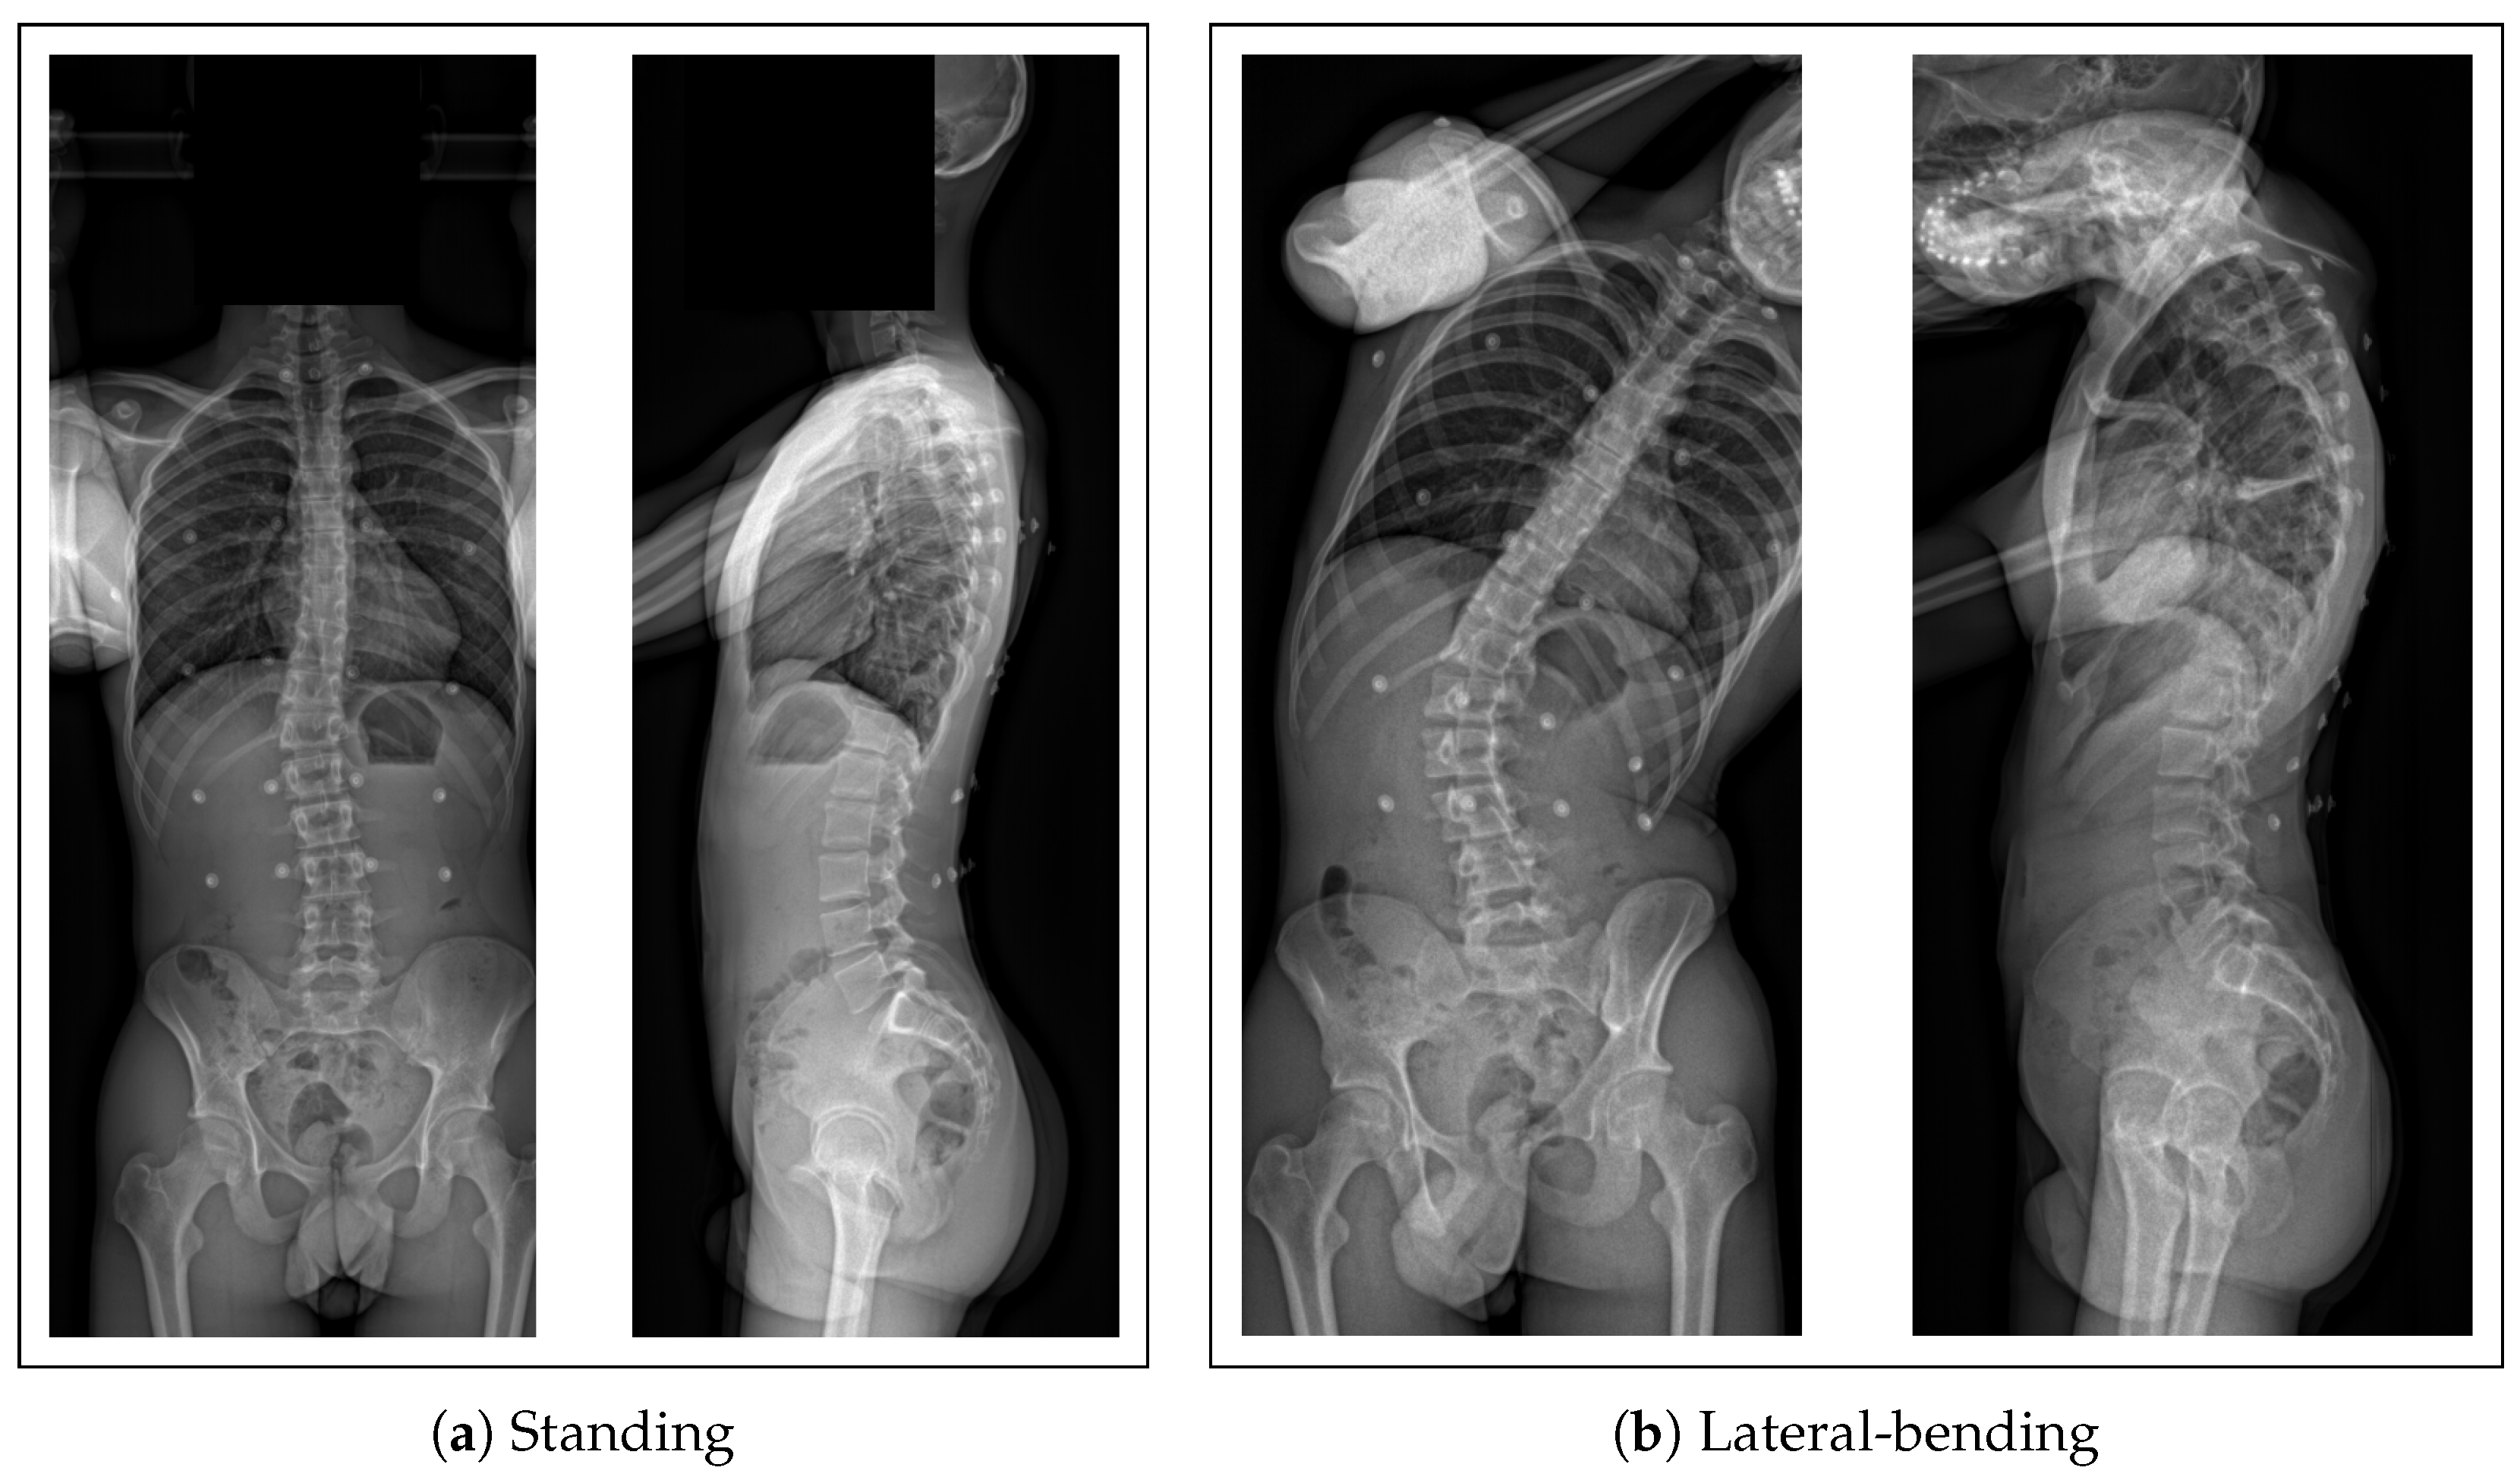

2.1. Collected Data

- A biplanar X-ray of their trunk made with an EOS imaging system

2.5. Validation of the Kinematic Predictions

3.2. Accuracy of the Subject-Specific Model in Bending

3.2.1. External Accuracy